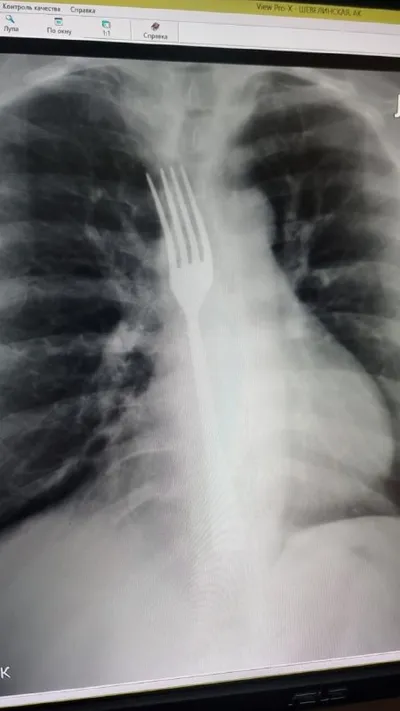

Девушка случайно проглотила вилку, пытаясь вызвать рвоту. Женщина столкнулась с проблемой – «встал желудок». Не найдя ничего лучше, она попыталась вызвать рвоту вилкой. Пара неловких движений – и при